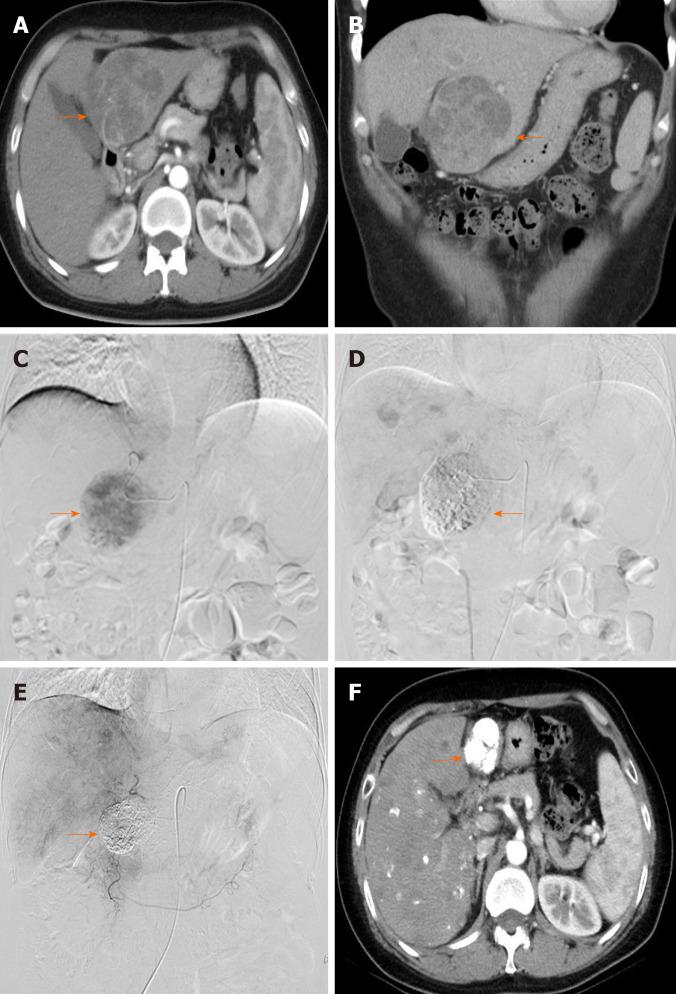

Sorafenib combined with embolization plus hepatic arterial infusion chemotherapy for inoperable hepatocellular carcinoma.

To investigate the safety and clinical outcomes of sorafenib combined with HAIC with folinic acid, 5-fluorouracil (5-FU), and oxaliplatin (FOLFOX) after TACE for intermediate and advanced HCC.

This prospective phase II study enrolled patients with intermediate and advanced HCC who underwent treatment with sorafenib combined with TACE-HAIC. All patients initially received the standard 400 mg dose of sorafenib twice daily before TACE-HAIC. Participants at our institute with intermediate and advanced HCC underwent routine TACE. Then, the catheter used for embolization was kept in place in the hepatic artery, and oxaliplatin was intra-arterially administered for 6 h, followed by 5-FU for 18 h, and folinic acid was intravenously administered for 2 h. The primary endpoints were safety, as evaluated by the Common Terminology and Criteria for Adverse Events version 4.0, and 12-mo progression-free survival (PFS), as analyzed by the Kaplan-Meier method. As secondary endpoints, the objective response rate (ORR) was evaluated by the modified Response Evaluation Criteria for Solid Tumors, and survival time [overall survival (OS)] was analyzed by the Kaplan-Meier method.